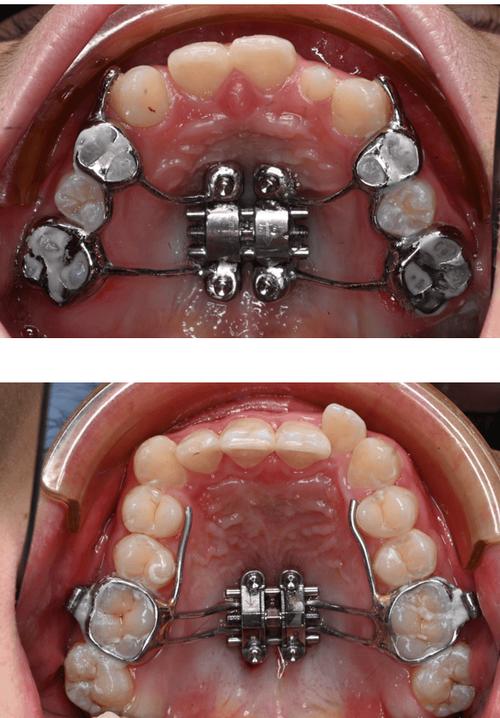

| 固定矫正器 | 通过粘接在牙齿上的托槽、弓丝及额外附件(如颌间牵引钩、微种植钉),施加持续、精准的生物力,直接移动牙齿并间接带动颌骨改建。 | 各年龄段骨性错颌,尤其是中重度骨性反颌、深覆颌、开颌等;常与正颌手术联合使用(成人患者)。 | 固定不可摘戴,矫正力可控性强;疗程相对较短(1.5-3年);需严格口腔卫生维护,避免托槽脱落及龋齿。 |

| 矫形矫正器 | 利用快速扩弓、前方牵引等装置,通过较大力度刺激颌骨缝的骨改建,快速改变颌骨宽度或位置关系。 | 青少年上颌发育不足(导致后牙反颌、面中份凹陷)、下颌发育不足(导致III类错颌)等,需在颌骨生长高峰期使用。 | 矫正力较大,短期效果明显;可能伴随暂时性疼痛、不适;需严格把控适应症,避免过度矫形导致颌骨损伤。 |

固定矫正器则通过“牙齿-颌骨-肌肉”的联动作用实现矫正:通过颌间牵引(上颌牙与下颌牙之间施加交互牵引力),将后牙向近中移动,同时带动下颌骨向前调整;利用微种植钉作为支抗,对颌骨进行整体移动或旋转,避免牙齿代偿性倾斜,无论是哪种矫正器,其最终目标都是通过持续、稳定的力,引导颌骨按照正常生长发育轨迹或理想位置进行改建,实现“面型、咬合、功能”的三重改善。